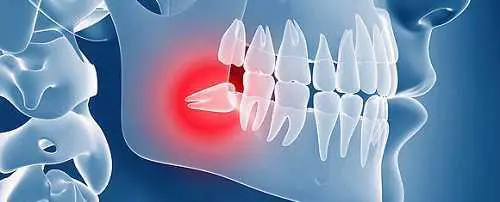

Cirugía de Terceros Molares (muelas del juicio):

Las muelas del juicio o terceros molares son de los principales motivos para la consulta con un cirujano maxilofacial, la extracción de estas piezas requieren de tratamiento quirúrgico ya que la posición de estas puede estar con una angulación no adecuada, o por la profundidad en que se encuentran y poder tener contacto con el nervio dentario, que es el que provee sensibilidad a los dientes, labio y mentón. Una extracción complicada puede acarrear varias complicaciones, desde infecciones, hasta fracturas de la mandíbula, lesiones en el nervio, o fragmentos o residuos del molar a extraer, es por eso que el cirujano maxilofacial el indicado para estos tratamientos por su formación quirúrgica así como para tratamiento de las complicaciones que se presenten.